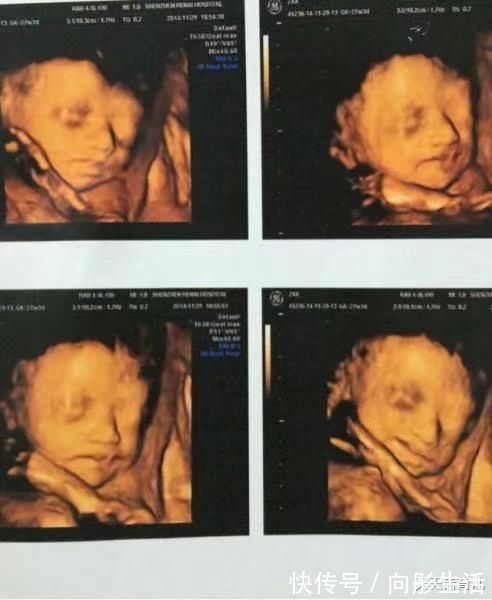

胎儿排畸检查

四维彩超是比较清晰的一种检查,可以看到胎儿的面部、四肢以及心脏等情况,通过体表检查,可以看出胎儿有无畸形,也是比较重要的一种排畸检查。